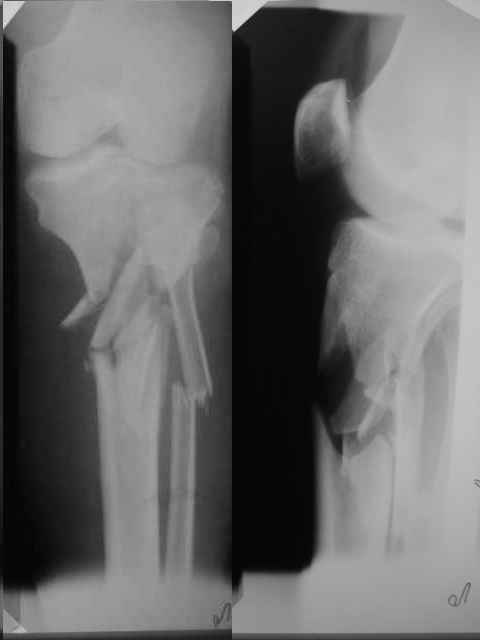

Вообще, лечение надо было начинать с таза. На голени можно ожидать большие проблемы уже через 2-3 месяца.

-На голени можно ожидать большие проблемы уже через 2-3 месяца-

А в чем будут заключаться проблемы? Замедленная консолидация или...

В лучшем случае - замедленная консолидация, а вообще - потеря репозиции, миграция винтов и/или перелом пластины. Внешняя иммобилизация не спасет.

Неудовлетворительная репозиция: вальгус, диастаз по медиальному кортикалу. Наверняка репозиция была открытой недели через две после травмы, а значит травматичной со скелетированием отломков. Наличие в диафизарной части пластины 7 ответстий не означает, что во все надо вводить винты. В метаэпифиз необходимо было ввести минимум 3 блокированных винта на всю толщу спонгиозы.

1. Репозиция должна быть закрытой непрямой. Репозиция основных отломков (не промежуточных!) по длине и по осям (варус\вальгус и т.д).

2. Фиксация - биологичная, по принципам относительной стабильности.

3. С гвоздем бы сюда не полез

4. В зависимости от состояния мягких тканей или аппарат, или LCP PLT (LISS) на 9 отверстий. Если пластина (как внутренний фиксатор), то 4-5 отверстий в зоне разрушения кости оставил бы без винтов, для репозиции использовал бы временный стержневой аппарат (АО, Зиммер, S&N,... - НО не МКЦ)

5. Только сначала бы разобрался с тазом